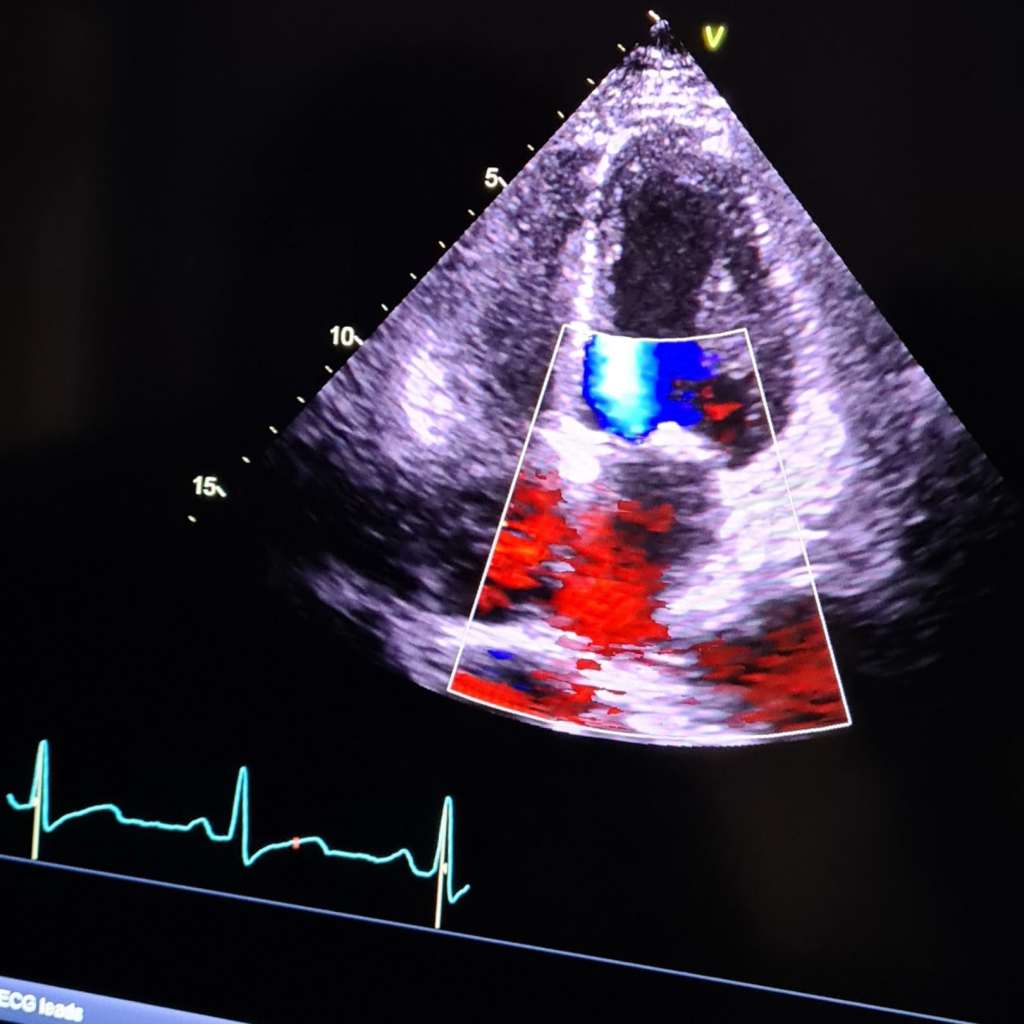

The Echo was on October 3rd. Again, this is another fascination for me to see the heart valves opening and closing it’s just amazing.